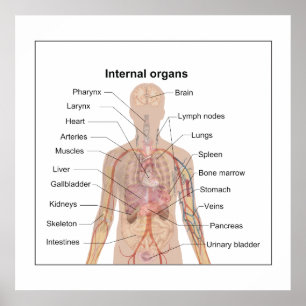

Chart of human internal organs

PriceCA$52.70